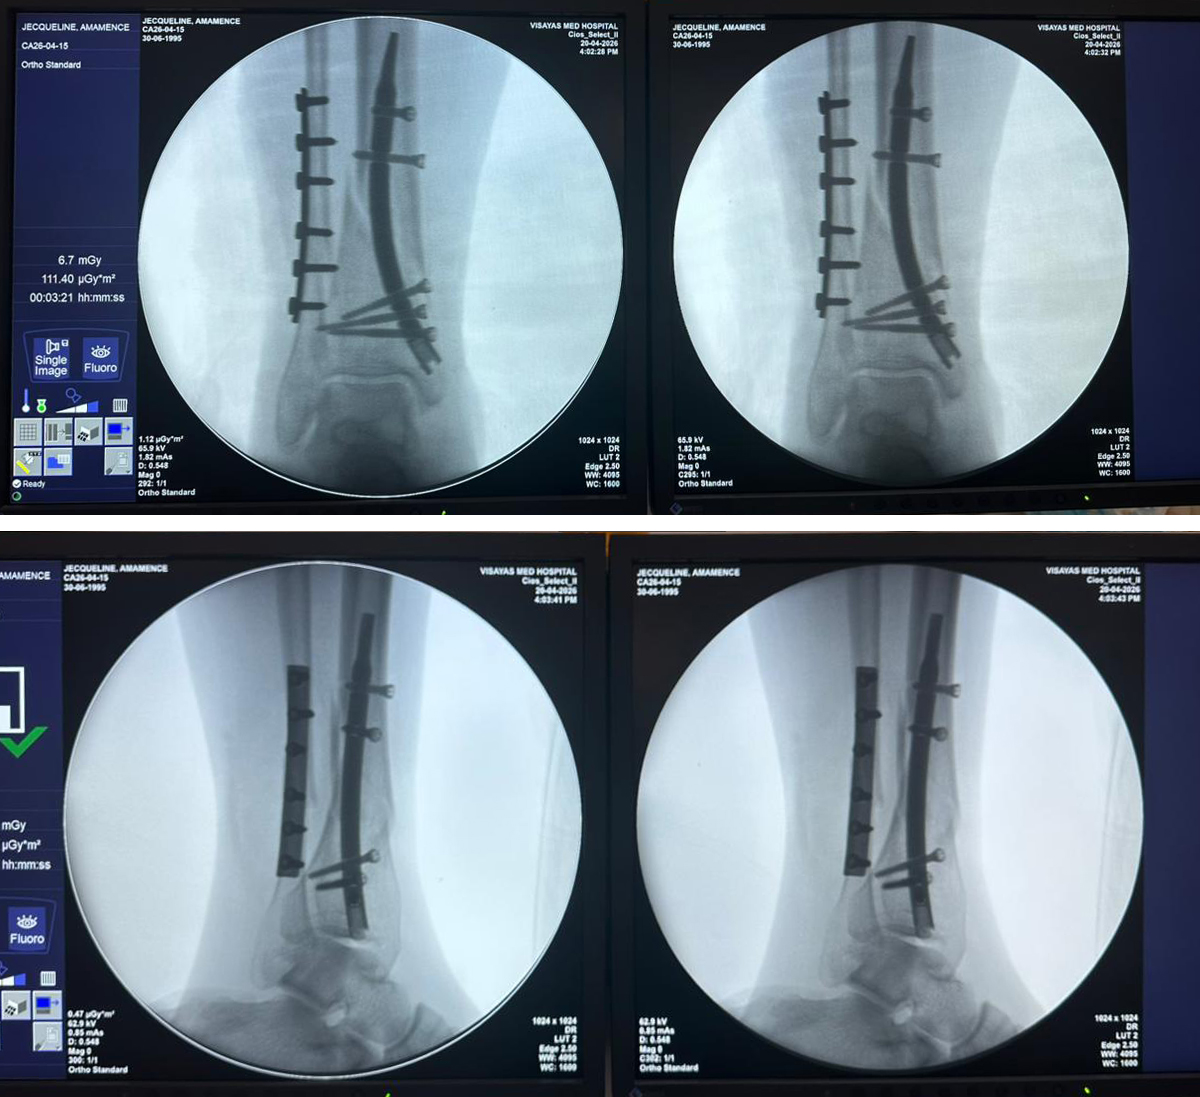

• Distaalinen sääriluun kynsi - 31 vuotta

Tämä tapaus esittelee 31-vuotiasta potilasta, jota hoidettiin distaalisen sääriluun kynnen kiinnityksellä distaalisen sääriluun ja pohjeluun murtuman vuoksi. Intraoperatiivinen C-varren fluoroskopia vahvisti intramedullaarisen naulan sijainnin, distaaliset lukitusruuvit ja fibulaarisen levyn kiinnityksen. Tapaus osoittaa distaalisen sääriluun kynsijärjestelmän käytön vakaaseen kiinnitykseen distaalisella sääriluun alueella, mikä tarjoaa kliinisen referenssin ortopedisille jakelijoille, sairaaloille ja kirurgisille ryhmille, jotka arvioivat sääriluun murtumien kiinnitysratkaisuja. Lue lisää